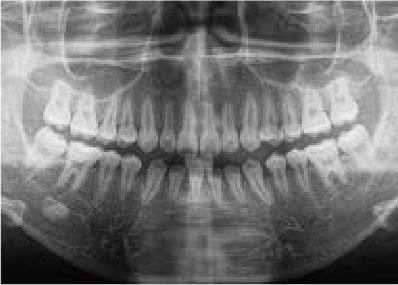

これから生えてくる永久歯のスペースがなく、歯が並ぶ余地がほとんどありませんでした。

さらに、上からあごの骨を見たところ、中央がくびれた“ひょうたん型”に変形しており、あごの成長にも偏りが見られました。

診断の結果、前歯の中心も少し左にずれており、特に犬歯が生えるスペースが足りない状態でした。

飲み込むときに下くちびるに力が入り、顔の左側にゆがみが出ている様子も確認できました。